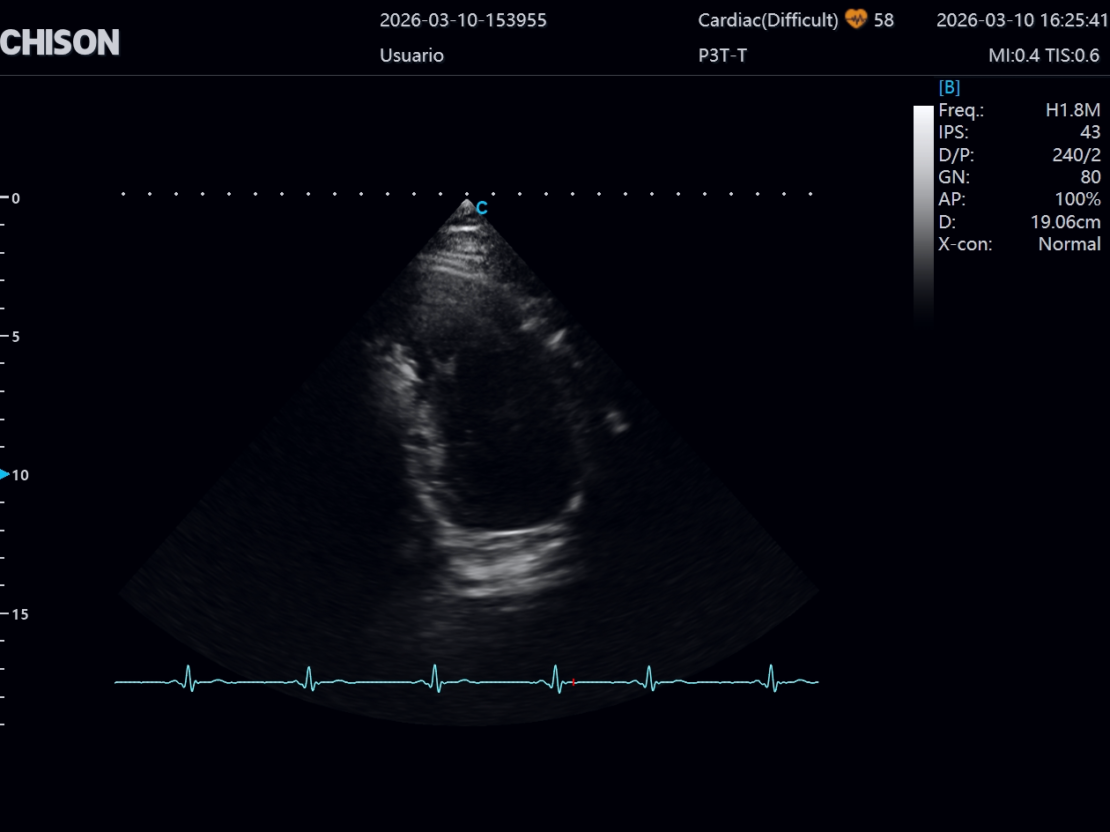

Importancia en ecocardiografía

En cardiología, esta tecnología mejora la capacidad del ultrasonido para evaluar en tiempo real:

- La función ventricular

- El movimiento del miocardio

- El funcionamiento de las válvulas cardíacas

- El flujo sanguíneo intracardíaco

- Alteraciones estructurales del corazón

Esto permite realizar evaluaciones cardíacas más precisas y confiables.

Ultrasonidos de nueva generación como el XBit 90 integran tecnologías avanzadas que mejoran el rendimiento clínico. Gracias al uso de transductores Single Crystal, permiten:

- Mayor detalle en estudios ecocardiográficos

- Mejor visualización de estructuras cardíacas complejas

- Evaluación más precisa del flujo sanguíneo